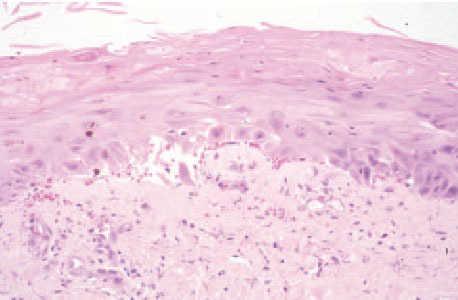

Se realizó una biopsia de tobillo izquierdo, en la que se encontraron cambios dismadurativos en la epidermis con imágenes de atipia celular y degeneración vacuolar en los queratinocitos de la capa basal (fig. 4). En la dermis se observaban algunos infiltrados inflamatorios linfocitarios perivasculares con frecuente extravasación hemática. En los conductos ecrinos existían imágenes focales de siringometaplasia (fig. 5). Se suspendió la administración de metotrexato y se instauró tratamiento con ácido folínico, con lo que se consiguió la resolución de todas las lesiones mucocutáneas.

Fig. 4. Paciente 2 . Biopsia en la que se observan cambios similares a los del primer paciente, destacando además degeneración hidrópica basal y extravasación hemática. (Hematoxilina-eosina, ×100.)